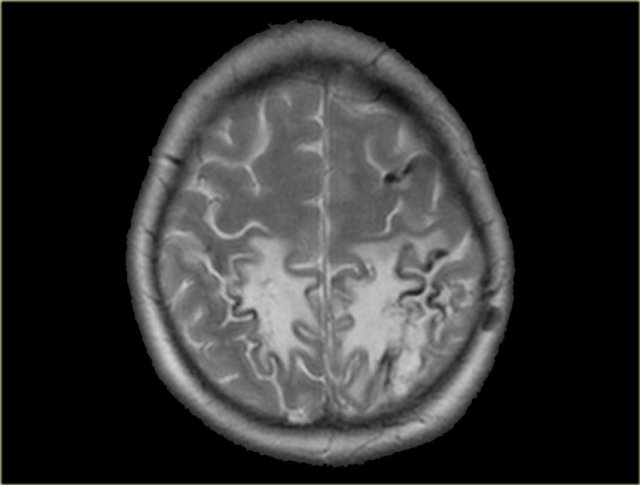

Venous infarction (5) - Edema

In some cases of venous thrombosis the imaging findings can resolve completely.

On the left a patient with a subcortical area of high signal intensity.

The first impression was that this could be a low grade glioma.

On a follow up scan the abnormalities had resolved completely.

In retrospect a dense vessel sign was seen in one of the cortical veins and the diagnosis of venous thrombosis was made.

The high signal intensity can be attributed to vasogenic edema due to the high venous pressure that resulted from the thrombosis.